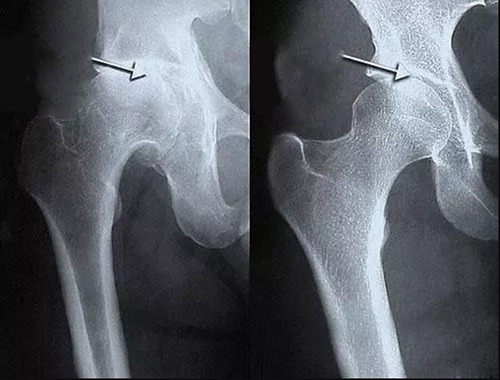

- แคลเซียมเกาะกระดูก (Osteophytes) คือตัวการของโรคข้อและกระดูกกว่า 97% เช่น โรคข้ออักเสบ โรคข้อเสื่อม โรคกระดูกอ่อน โรคกระดูกพรุน โรคไขข้ออักเสบ โรคถุงน้ำในข้ออักเสบ และแม้แต่ซีสต์ของปมประสาท

นี่เป็นเพียงรายชื่อโรคอย่างย่อเท่านั้น โรคอื่น ๆ ล้วนเป็นเพียงกลุ่มย่อยของพยาธิสภาพหลักทั้ง 9 ประเภท เช่น โรคข้อสะโพกเสื่อม (Coxarthrosis) ก็เป็นชนิดหนึ่งของโรคข้อเสื่อม (Osteoarthritis) เป็นต้น